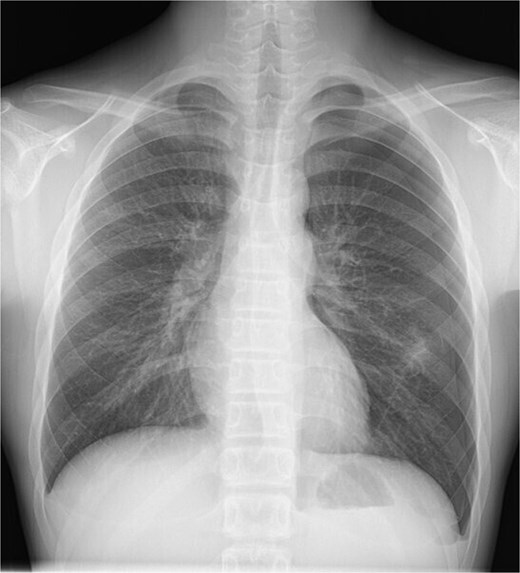

A 13-year-old boy presented with chest pain and dyspnea. There was no significant medical or family history. Chest radiography showed a left pneumothorax and opacity in the left middle lung field (Fig. 1). Computed tomography (CT) showed a left pneumothorax and a bony, pedunculated mass arising from the fifth rib. The cortical bone and bone marrow continued to move away from the fifth rib (Fig. 2). The mass was slim, pedunculated, and pointed directly inward to the thoracic cavity (Fig. 3), and it was suspected to have invaded the left upper lobe of the lung. There were no bullae, and the patient had no history of trauma. The patient was diagnosed with pneumothorax due to a costal osteochondroma. The patient was admitted to our hospital and underwent surgery to remove the costal osteochondroma and treat the left pneumothorax. Three-port video-assisted thoracic surgery revealed no bullae but a bony and pedunculated osteochondroma arising from the anterior aspect of the fifth rib (Fig. 4). There was a wound in the left lingular segment and a thickened visceral pleura around the wound (Fig. 5). We performed wedge resection of the lingular segment, including the wound and thickened visceral pleura. We removed the osteochondroma during thoracoscopic surgery without partial rib resection using electrocautery and Cooper scissors. A water-sealing test revealed no air leakage.

Chest radiography showing a left pneumothorax and an opacity in the left middle lung field.